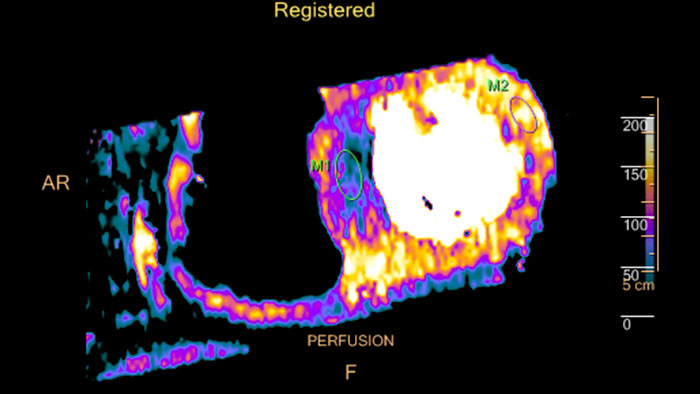

Fusing cardiac CT-MI images

Cardiac CT-MI Fusion incorporates support for myocardial perfusion imaging (MPI).

un-gated stress MI datasets simultaneously with the CT.

Dynamic color maps provide an assessment of myocardial risk

Provides automatic and manual tools to help visualize and assess signal intensity differences (in Hounsfield Unit) focusing on the left ventricular myocardium, providing quantitative myocardial perfusion measurements for CT images.